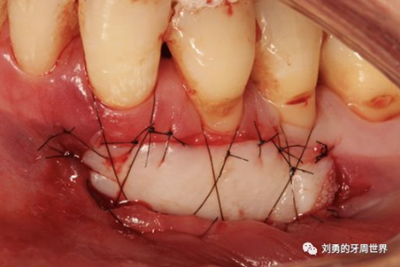

比如strip技術(shù),如下圖:

上圖中,種植體唇側(cè)缺乏附著齦,從上腭取瓣,常規(guī)做法:取長而寬的齦瓣,這樣供區(qū)面積大,術(shù)后疼痛重。

為了減少痛感,從雙側(cè)上腭取多條長而窄的齦瓣進(jìn)行移植,這樣每個供區(qū)的傷口都比較窄,可以減少術(shù)后的痛感。